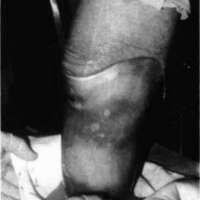

The socket is sanded lightly on the inside to promote adherence of the alginate, and escape holes are drilled medially and laterally approximately one inch proximal to the distal end. Small pin holes are also drilled over void areas to allow air to escape as the alginate fills. The water and powder are mixed with an electric drill and paint stirrer, and then poured into the test socket and slushed around the walls to completely coat the inside of the socket. The patient then enters the socket and stands with equal weight-bearing bilaterally. The alginate fills void areas, establishing total contact. The excess is evacuated, and gelling occurs in one to three minutes (Fig. 4 and Fig. 5). The patient is then seated and the socket is carefully removed, after breaking the suction seal. The alginate will adhere to the inside of the socket.

Figure 4. Alginate fills void areas while patient bears one half of his weight into the socket. Excess alginate flows through small relief holes drilled for this purpose.Figure 5. Alginate solution cures between one and three minutes.